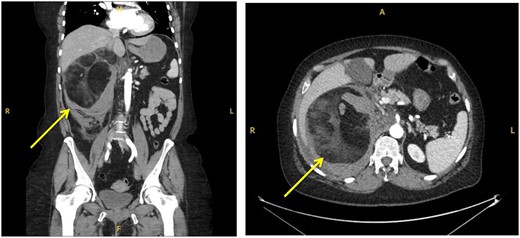

A 55-year-old Caucasian female presented to the emergency department (ED) after falling from sitting on a static pushbike onto her right flank. She immediately incurred right flank pain with nil other symptoms at time of the event. Her medical history was insignificant and she did not take any regular medications. Blood tests on admission indicated there may be an intra-abdominal injury due to raised lactate of 3 and a blood pH of 7.304. An urgent CT abdomen and pelvis (CTAP) with contrast was performed which showed a large (15.2×13.8 cm), predominantly fat containing mass in the right suprarenal region causing displacement of the right kidney and pancreas, with surrounding hyperdense fluid suggestive of acute retroperitoneal haemorrhage (Fig. 1).

Coronal (a) and transverse (b) sections of initial CT imaging with contrast showing large lesion with heterogeneous hypodense areas with surrounding haematoma (arrowed).